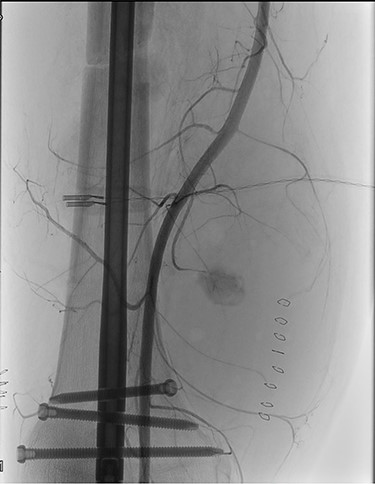

At the Doppler examinations after 2 and 12 months, triphasic-flow of the entire vascular artery axe of the lower right limb was detected (Fig. 4).

Duplex ultrasound made after 2 months, showing triphasic flow of the right popliteal artery.